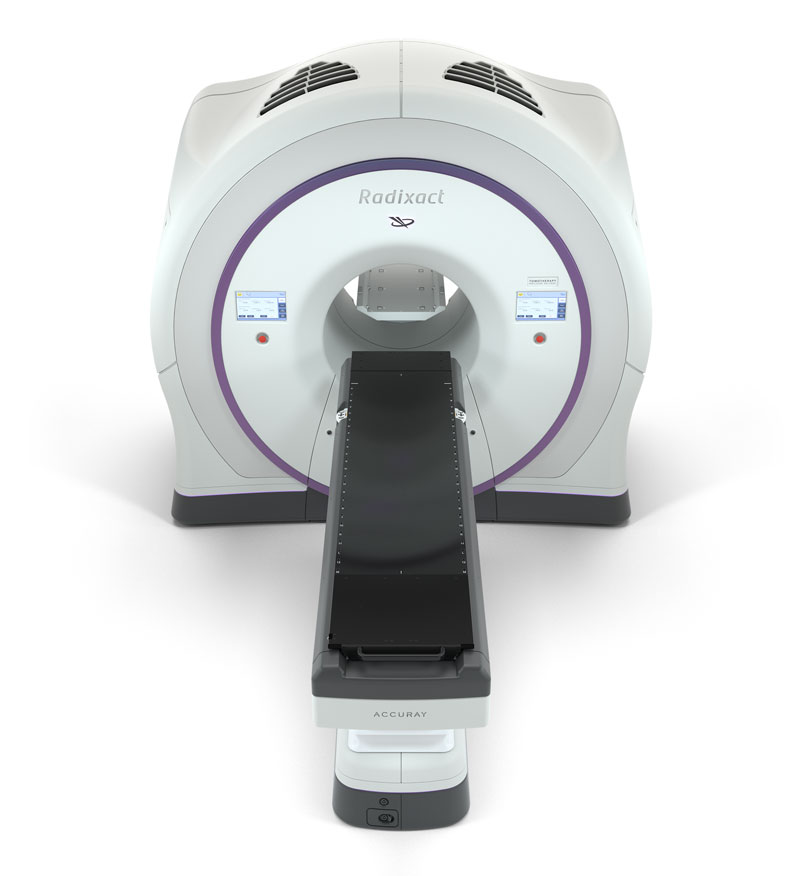

Breast Cancer Biology for the Radiation Oncologist (Medical。Breast Cancer - Radixact。Breast Cancer: Cellular and Molecular Biology | SpringerLink。新潟県産コシヒカリ 10kg 早い者勝ち。